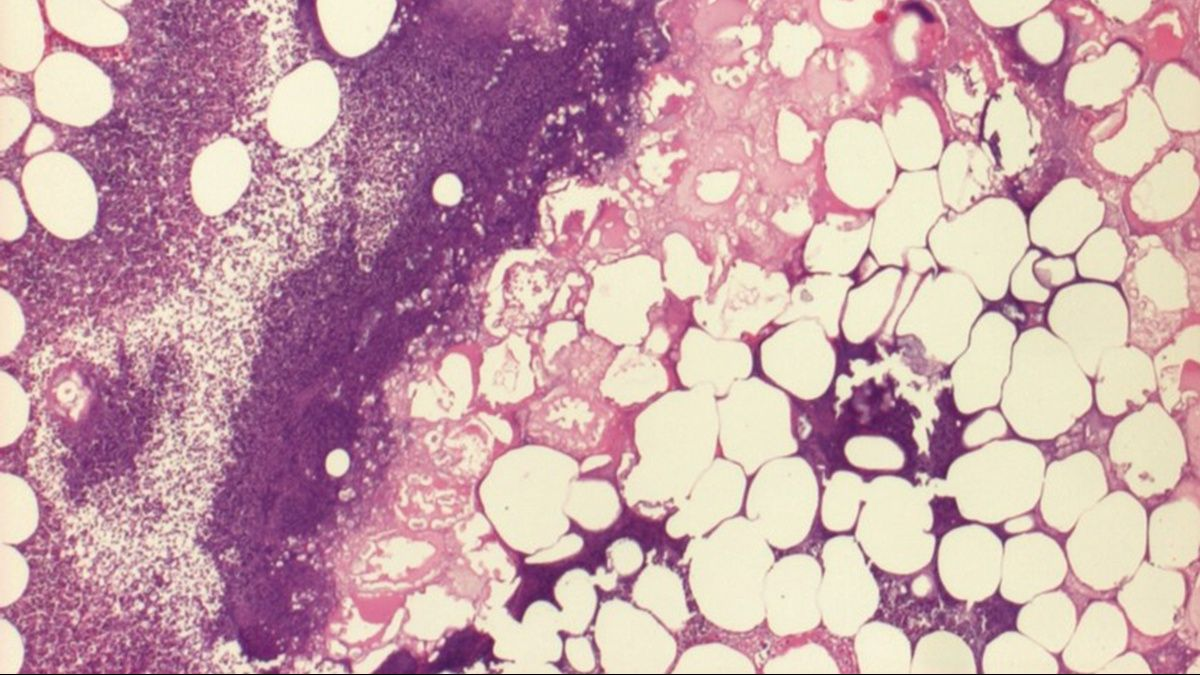

Viele Katzen mit Typ-2-Diabetes leiden unter gering- bis hochgradiger Adipositas (Abbildung 1). Ihre Ernährung muss daher auf eine spezielle Nahrung umgestellt werden, die spezifisch auf eine Gewichtsreduktion abzielt. Wichtig ist jedoch eine kontrollierte Gewichtsabnahme, so dass die Gesundheit der Katze erhalten bleibt, wobei die gewählte Nahrung die glykämische Last begrenzen muss. Im typischen Fall hat eine solche Nahrung eine niedrige Energiedichte, einen hohen Faser- und Proteingehalt sowie einen niedrigen Anteil löslicher Kohlenhydrate. Darüber hinaus sollte eine Nahrung für diabetische Katzen mit Antioxidanzien und L-Carnitin angereichert sein. Eine Nahrung mit niedriger Energiedichte gestattet es dem Besitzer zudem, größere Volumina zu füttern und so die Aufrechterhaltung der Sattheit zwischen den Mahlzeiten zu fördern. Unterstützt wird der Erhalt der Sattheit durch einen erhöhten Gehalt an unlöslichen Fasern in der Nahrung. Die Fraktion der löslichen Fasern in der Nahrung verlangsamt die Aufnahme von Nährstoffen und unterstützt auf diesem Weg die Kontrolle der glykämischen Last. Ein hoher Proteingehalt ist erforderlich, um einen Muskelabbau infolge der Kalorienrestriktion in der Nahrung zu vermeiden. Hier besteht ein synergistischer Effekt mit erhöhter körperlicher Aktivität (siehe unten) zur Förderung der Entwicklung der fettfreien Körpermasse. Antioxidanzien wirken den negativen Effekten Diabetes-assoziierter chronischer Entzündungen entgegen, und L-Carnitin fördert die vermehrte zelluläre Nutzung von Fett anstelle von Glukose als Energiequelle.

Die meisten Katzen mit Typ-2-Diabetes sind mindestens geringgradig adipös. Entscheidend ist, dass diese Patienten eine spezifisch auf die Förderung der Gewichtsreduktion ausgelegte Nahrung erhalten.

Abbildung 1. Die meisten Katzen mit Typ-2-Diabetes sind mindestens geringgradig adipös. Entscheidend ist, dass diese Patienten eine spezifisch auf die Förderung der Gewichtsreduktion ausgelegte Nahrung erhalten.© Shutterstock